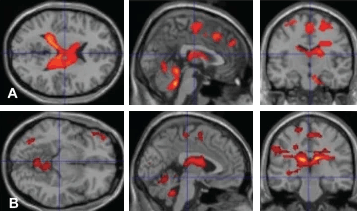

Нейровизуализация со спецэффектами: функциональная МРТ (фМРТ)

Ученым и врачам хотелось большего: видеть сквозь череп не только структуру, но и работу живого мозга [77]. Первые предпосылки появились в конце 19-го века: итальянский врач Анджело Моссо наблюдал за головным мозгом пациента через дефект в черепе и заметил, что пульсация мозговых сосудов усиливалась в разных участках мозга, когда пациент слышал звон колоколов или читал молитву — активация мозга для обработки внешнего сигнала требует больше кислорода, что усиливает кровоток (рис. 21А) [78].

В 1936 году Л. Полинг, известный своим открытием вторичной структуры белка [79], установил, что гемоглобин, насыщенный и обедненный кислородом, по-разному взаимодействует с магнитным полем. Наконец, в 1990 году команда японского биофизика Сэйдзи Огавы объединила все эти знания и разработала принцип BOLD-контраста, то есть локального изменения МР-сигнала в зависимости от степени насыщения гемоглобина крови кислородом. Чем активнее нейроны, тем больше они забирают кислород у гемоглобина. На помощь японским ученым пришли животные и уже известные методы: они заставили крыс дышать воздухом с разным содержанием кислорода и сопоставляли изменения ЭЭГ-активности с МРТ-изображениями [80]. Так зародились основы функциональной МРТ — инструмента, который в реальном времени показывает, какие зоны «вспыхивают», когда мы читаем, лжем или решаем головоломки (рис. 21Б). В основе метода лежит оценка изменения активности нейронов по локальному изменению кровотока в покое и при выполнении различных задач. Разработка фМРТ очень пригодилась в нейрохирургии для индивидуального планирования операций, а также выявила ключевые нервные контуры, отвечающие за различные функциональные состояния головного мозга [77].

Функциональная МРТ (фМРТ) —

- разновидность магнитно-резонансной томографии, которая по изменению уровня оксигенации (насыщения кислородом) крови позволяет в режиме реального времени визуализировать активность нейронов головного мозга в ответ на внешние раздражители или выполнение задач.